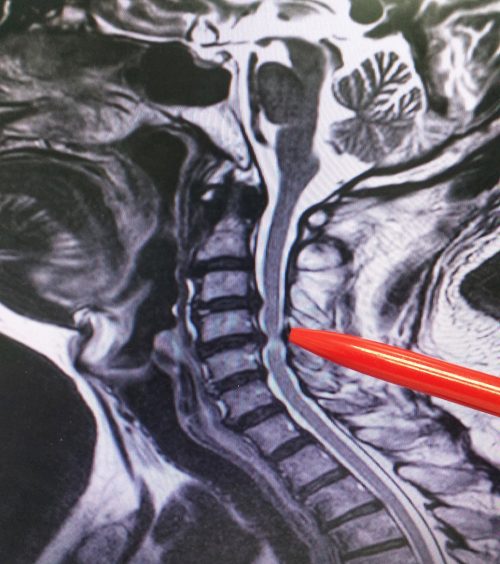

What is a Posterior Cervical laminectomy or Decompression?

In a cervical laminectomy procedure, a small section of bone that covers the back of the spinal cord, called the lamina, is removed. The removal of this portion of the bone and any nearby bone spurs relieves the pressure on the spinal cord or nerves that go down the arms.

Depending on the extent of the damage, the lamina may be removed in portions or in its entirety on both sides of the spine. By removing the lamina, bone spurs and other overgrowth, the compression of the spinal cord and spinal nerves is alleviated and symptoms improve.